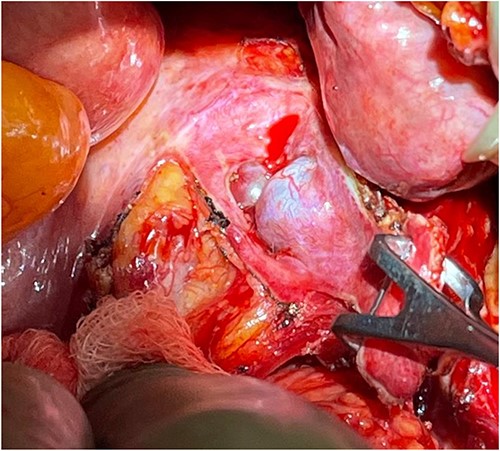

Patient underwent laparotomy with en bloc resection of pararectal mass with right lateral mesorectum, right Fallopian tube and ovary (Fig. 4). A complete iliac lymphadenectomy was executed as multiple necrotic lymph nodes were found along the common iliac vessels. The mass was removed with negative macroscopic margins, free from the rectum wall (Fig. 5). Presacral drainage and disk debridement was completed for refractory osteodiscitis. Four months later, patient underwent total thyroidectomy with selective parathyroidectomy.

Perioperative location of the tumor, as the rectum is being retracted to the left (by hand).